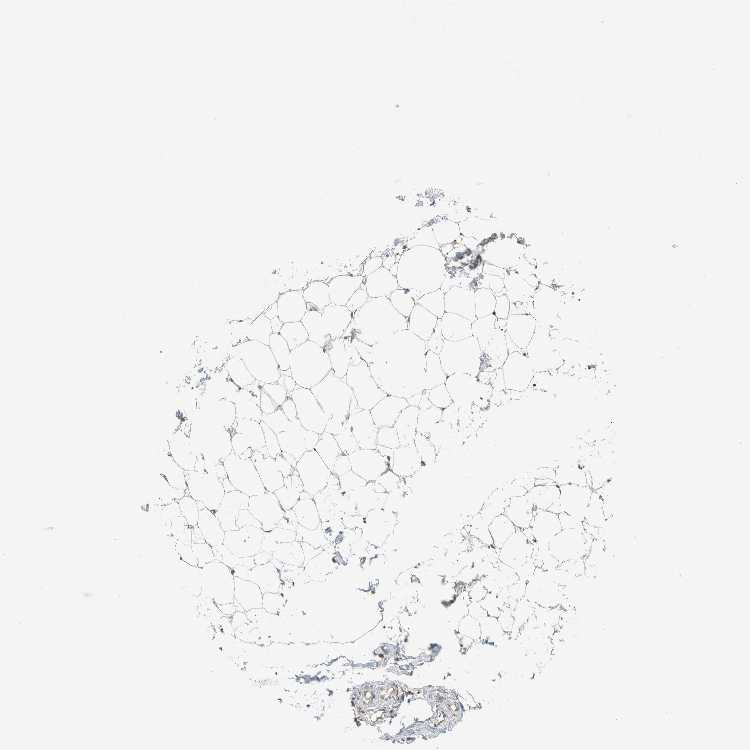

SOFT TISSUE 1 - Antibody stainingi

Antibody staining in the annotated cell types in the current human tissue is reported as not detected, low, medium, or high, based on conventional immunohistochemistry profiling in selected tissues. This score is based on the combination of the staining intensity and fraction of stained cells.

Each image is clickable and will lead to virtual microscopy that enables deeper exploration of all samples and also displays staining intensity scores, fraction scores and subcellular localization as well as patient and tissue information for each sample.

Antibody HPA024103

Chondrocytes High

Fibroblasts Medium

Peripheral nerve Not detected